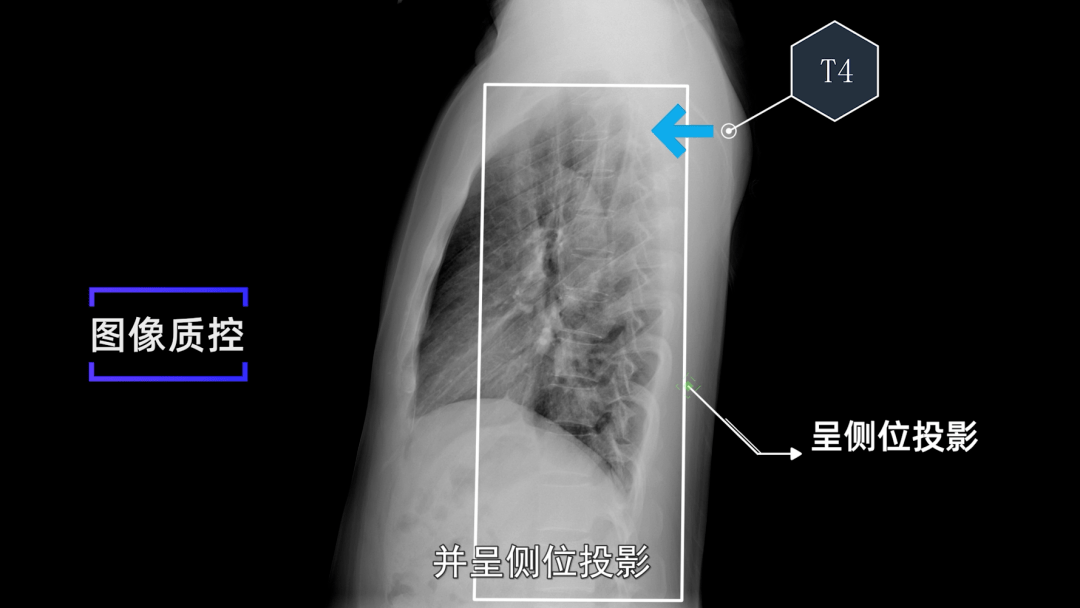

x线规范化检查 | 胸部正侧位摄影(视频及图文详解)

侧位胸 片latealrvie w暗盒 -rax cysaestte 缺:点不能动 观态察

胸部摄片 后前位 侧位